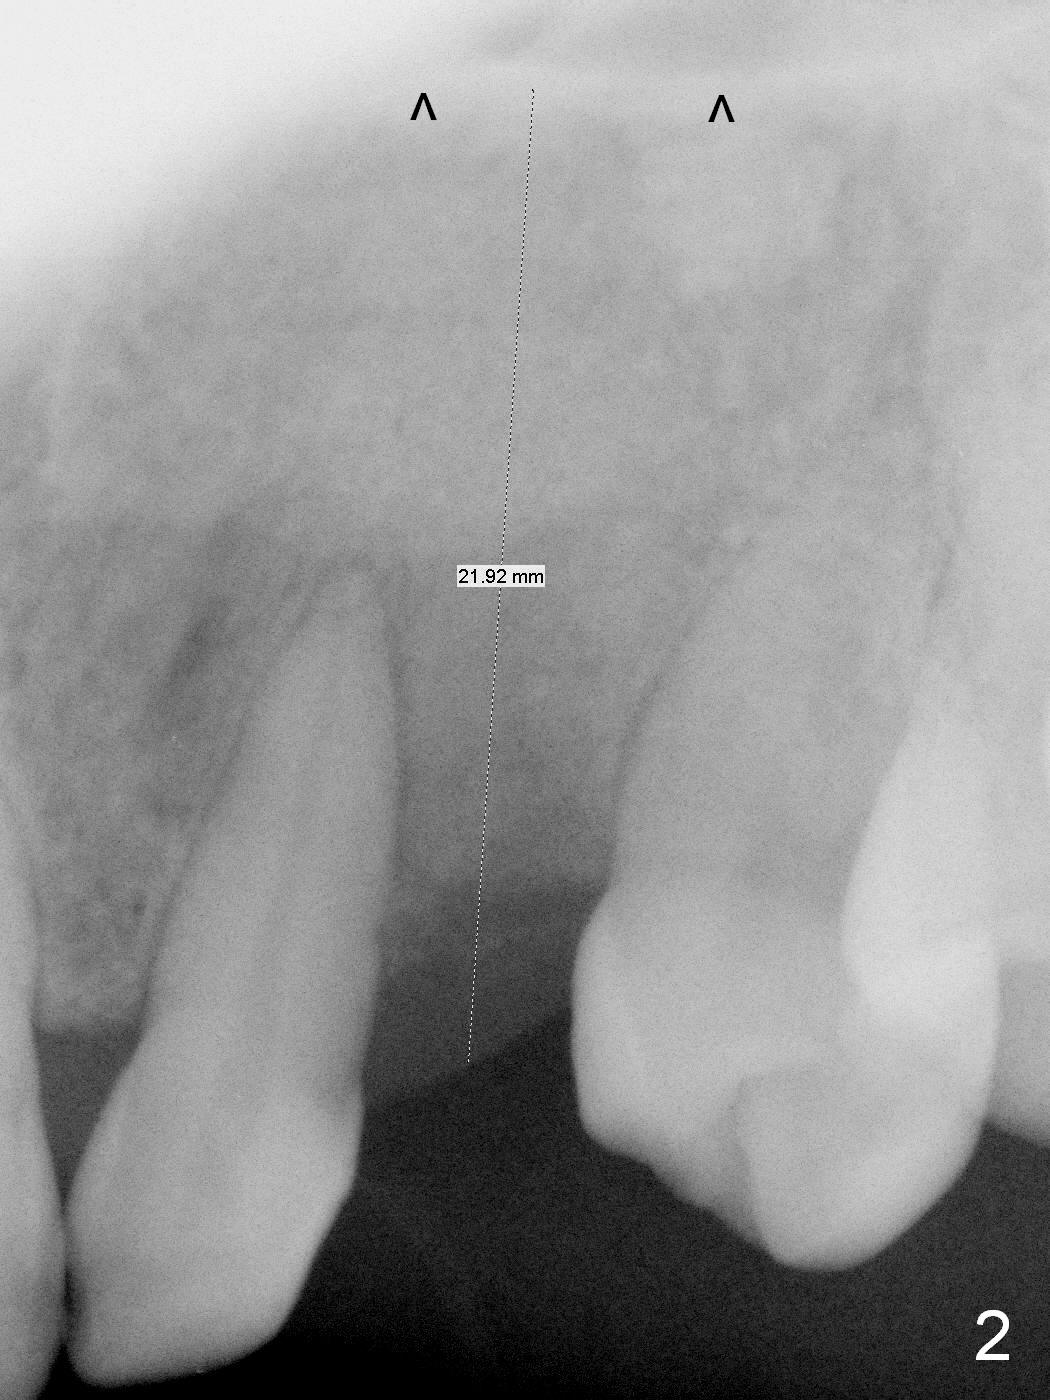

The ridge looks wide clinically 4 months post implant removal and socket preservation. In fact, the graft bone is soft and the ridge is narrow after incision. It appears that an angled 1 piece implant is an indication. A 1.2 mm pilot drill is used to start osteotomy. At approximately 17 mm, the patient feels pain. The nasal floor perforates? A 2 mm osteotome is utilized to enlarge the osteotomy. At 17 mm, the osteotome is stable (Fig.1), but the nasal floor appears out of view. Review of the preop PA shows that the distance between the gingival margin and the nasal floor (arrowheads) is ~22 mm (Fig.2). It should be safe and necessary to place a 3x20 mm 1-piece implant with 15° angulation. Insertion torque is between 40 and 45 Ncm.

Eight months postop, the patient returns for #11 restoration. She reports no problem at #11, while there is light tenderness with a 2-piece implant (4.5x20 mm) at #6 at night (Fig.10, a portion of panoramic X-ray). Clinical exam reveals no abnormality at #6. Although the implant at #11 is buccally placed, there is no buccal plate atrophy (Fig.6,7). In fact the 20 mm 1-piece implant is placed in the bone (septum) between the nasal cavity (Fig.10 pink dashed line; Fig.13 (CBCT (52 year-old lady) N) and the maxillary sinus (yellow dashed line, S). In fact the apparent nasal floor indicated as arrowheads in Fig.2 and 10 is the horizontal plate of the palatine bone (hard palate)! Therefore there is no nasal floor perforation in this case. A long implant is indicated in the upper canine.